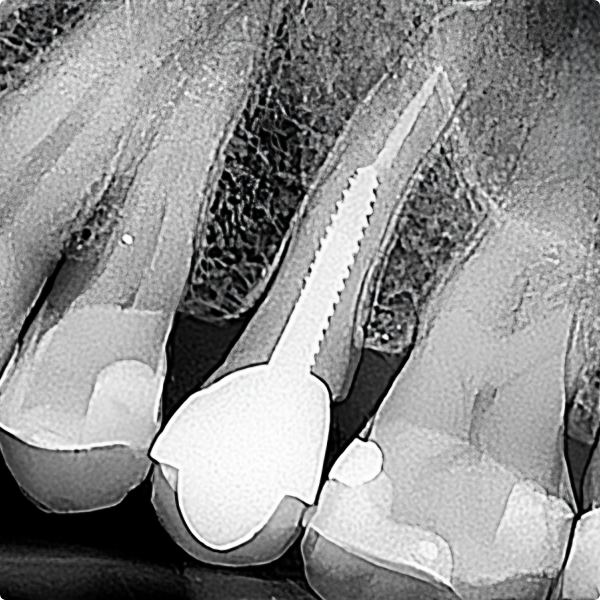

Traditional intraoral sensors rely on scintillators to convert X-rays into visible light before being captured by the sensor. While effective, this multi-step process can introduce noise and diminish image quality.

Direct conversion technology in the NewTom DCiS works differently:

For dentists, this isn’t just about technology; it’s about empowering your clinical judgment. With the NewTom DCiS you can diagnose with confidence on the first scan, minimise repeat exposures, and focus on the best outcomes for your patients.

Clear, high-contrast images aren’t just a convenience - they’re essential. Every detail captured by the NewTom DCiS can make the difference between a timely intervention and a missed complication.